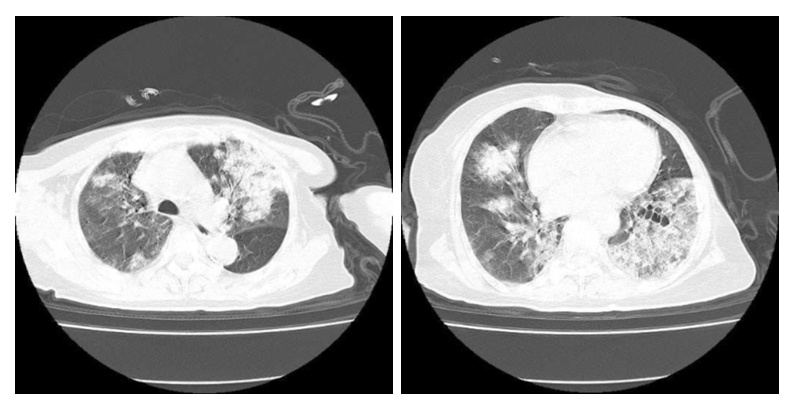

患者经验性抗感染治疗后症状进行性加重,仍诉咳嗽咯血,胸闷气促,无发热。氧合指数进行性下降(最低值102),经会诊后于2022-03-24转入ICU,予经鼻高流量氧疗(FiO2: 90%,流速50 L/min)。复查血常规:WBC 8.57×109/L、HGB 69.00 g/L、PLT 141.00×109/L。CRP 90.14 mg/L,PCT 0.44 ng/mL,IL-6 211.40 pg/mL。Scr 141.43μmol/L、UA 372.60 μmol/L、BUN 12.87 mmol/L。凝血功能:D-二聚体0.57 μg/mL、余正常。心肌酶谱和肌钙蛋白正常,核周型抗中性粒细胞胞浆抗体(典型)阳性、抗核抗体(ANA)强阳性、ANA滴度1∶320(正常参考值< 1∶100),天然SS-A抗体强阳性、抗Ro-52抗体强阳性、抗SS-B抗体强阳性,抗心磷脂抗体阴性。血气示:pH 7.388、PaCO2 32.6 mmHg、PaO2 77.9 mmHg(FiO2 90%)、BE-5.4 mmol/L、HCO3- 19.6 mmol/L、Lac 1.6 mmol/L。支气管镜灌洗液呈血性,提示大量含铁血黄素组织细胞。3次痰培养抗酸染色、革兰氏染色阴性,2次血和痰培养未见细菌和真菌。胸部DR:两肺见广泛片絮状高密度影,右肺见片状实变影,较前明显进展(图 2A)。结合患者胸片和肺部CT表现,考虑急性重症狼疮性肺炎,弥散性肺泡出血。停美罗培南,改用哌拉西林他唑巴坦钠(4.5 g, ivgtt, q8h)+伏立康唑(0.2 g, ivgtt, q12h)+SMZ(2片,po,q12h)预防院内感染、真菌感染及非典型病原体感染,继续予甲泼尼龙静脉注射(40 mg,qd)治疗。

| A:2022-03-24检查示两肺见广泛片絮状高密度影,右肺见片状实变影,较2022-03-22前明显进展;B:2022-03-29检查示双肺见散在片絮状高密度影,双侧肋隔角锐利,较022-03-24明显改善 图 2 患者胸部DR检查影像 |

患者仍然诉胸闷,呼吸窘迫、咯血,伴有血色素进行下降,2次粪便隐血试验阳性。患者既往有股骨头坏死和肿瘤病史,拒绝激素冲击和免疫制剂治疗。为尽快改善症状,行血浆置换术(3 000 mL,qd),继续维持甲泼尼龙原治疗,加强护胃。经过连续5次血浆置换后,呼吸困难、咳嗽明显改善,无咯血。2022-03-29患者高流量吸氧改为普通吸氧,3.0 L/min,各项检查值:SaO2 97%~99%,WBC 8.16×109/L、中性粒细胞计数(NEUT)7.56×109/L、HGB 82.00 g/L。CRP 7.06 mg/L,IL-6 4.10 pg/mL,PCT 0.16 ng/mL,ESR 15.1 mm/h,Scr 111.20 μmol/L,总胆红素(TBIL)26.62 μmol/L、白蛋白(ALB)39.32 g/L、肝功能、电解质正常。核周型抗中性粒细胞胞浆抗体(典型)弱阳性、抗核抗体(ANA)强阳性、ANA滴度1∶100,天然SS-A抗体弱阳性、抗Ro-52抗体弱阳性、抗SS-B抗体弱阳性,抗心磷脂抗体阴性。胸部DR提示:双肺见片絮状高密度影,较前改善(图 2B)。2022-03-31复查胸部CT提示:双肺见多发磨玻璃样及片状高密度影,部分实变,较前吸收好转(图 3)。患者自动出院,出院口服泼尼松(40 mg,1次/d)和羟氯喹(200 mg,2次/d)治疗,并序贯减量,出院后2周(见附图 1A和图 1B)以及第6周胸部CT(见附图 1C和图 1D)随访较前进一步改善。